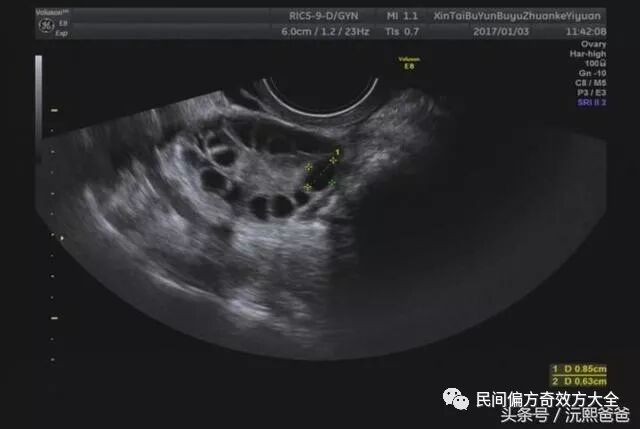

第一个就是:彩超检查。其实,更好的是内(阴)超检查。因为更加清晰地可以看出两侧的卵巢是否呈现多囊的状态。因为多囊卵巢用大白话来说,就是卵泡长不大或者是不排卵,在卵巢上集聚在一起,使得卵巢越来越大,彩超检查的时候,卵巢有超过十个以上的小卵泡就可以确证为多囊。

2. 彩超检查直接确诊多囊卵巢。